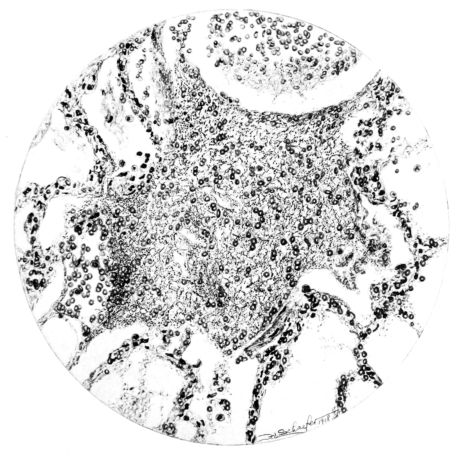

FIG. II. AUTOPSY NO. 98. DRAWING OF A SECTION THROUGH A TRACHEA SHOWING NECROTIZING HEMORRHAGIC INFLAMMATORY PROCESS OF THE MUCOSA.

The changes are less marked, perhaps, in the trachea than in its finer ramifications. The mucosa is constantly more or less destroyed and large areas, usually focal, are entirely devoid of their epithelial covering. This is replaced by a sparse exudate, composed largely of red blood cells, mucus, a small amount of fibrin, and nuclear fragments (Fig. II). It may dip into the submucosa for a short distance, but usually these indentures are associated with the ducts of the mucous glands into which the inflammatory reaction extends. A more striking feature than the exudate, however, is the edema and the congestion of the submucosa. The loose areolar tissue of the submucosa is spread widely apart, and throughout it distended blood vessels are very conspicuous. Occasionally such a vessel is broken and actual hemorrhage appears in the submucosa. Occasionally, too, the inflammation extends down the duct to the mucous gland itself, and here, also, aplastic inflammatory reaction is evident, inasmuch as the acini now stain intensely red with the cells undifferentiated from each other and specked here and there by broken remains of the dead nuclei (Fig. III). After the disease has continued for a short period, even at the end of five or six days, some regeneration of the epithelial lining may be seen (3) (Fig. IV). But despite this, the acute picture persists, and there goes on, side by side, an attempted repair characterized by epithelial regeneration and the same evidence of acute change. Since the lesion is essentially a superficial one, scars or contractures of any extent are not encountered in the trachea, even in examples of the disease that have ended fatally only after many weeks.[4]